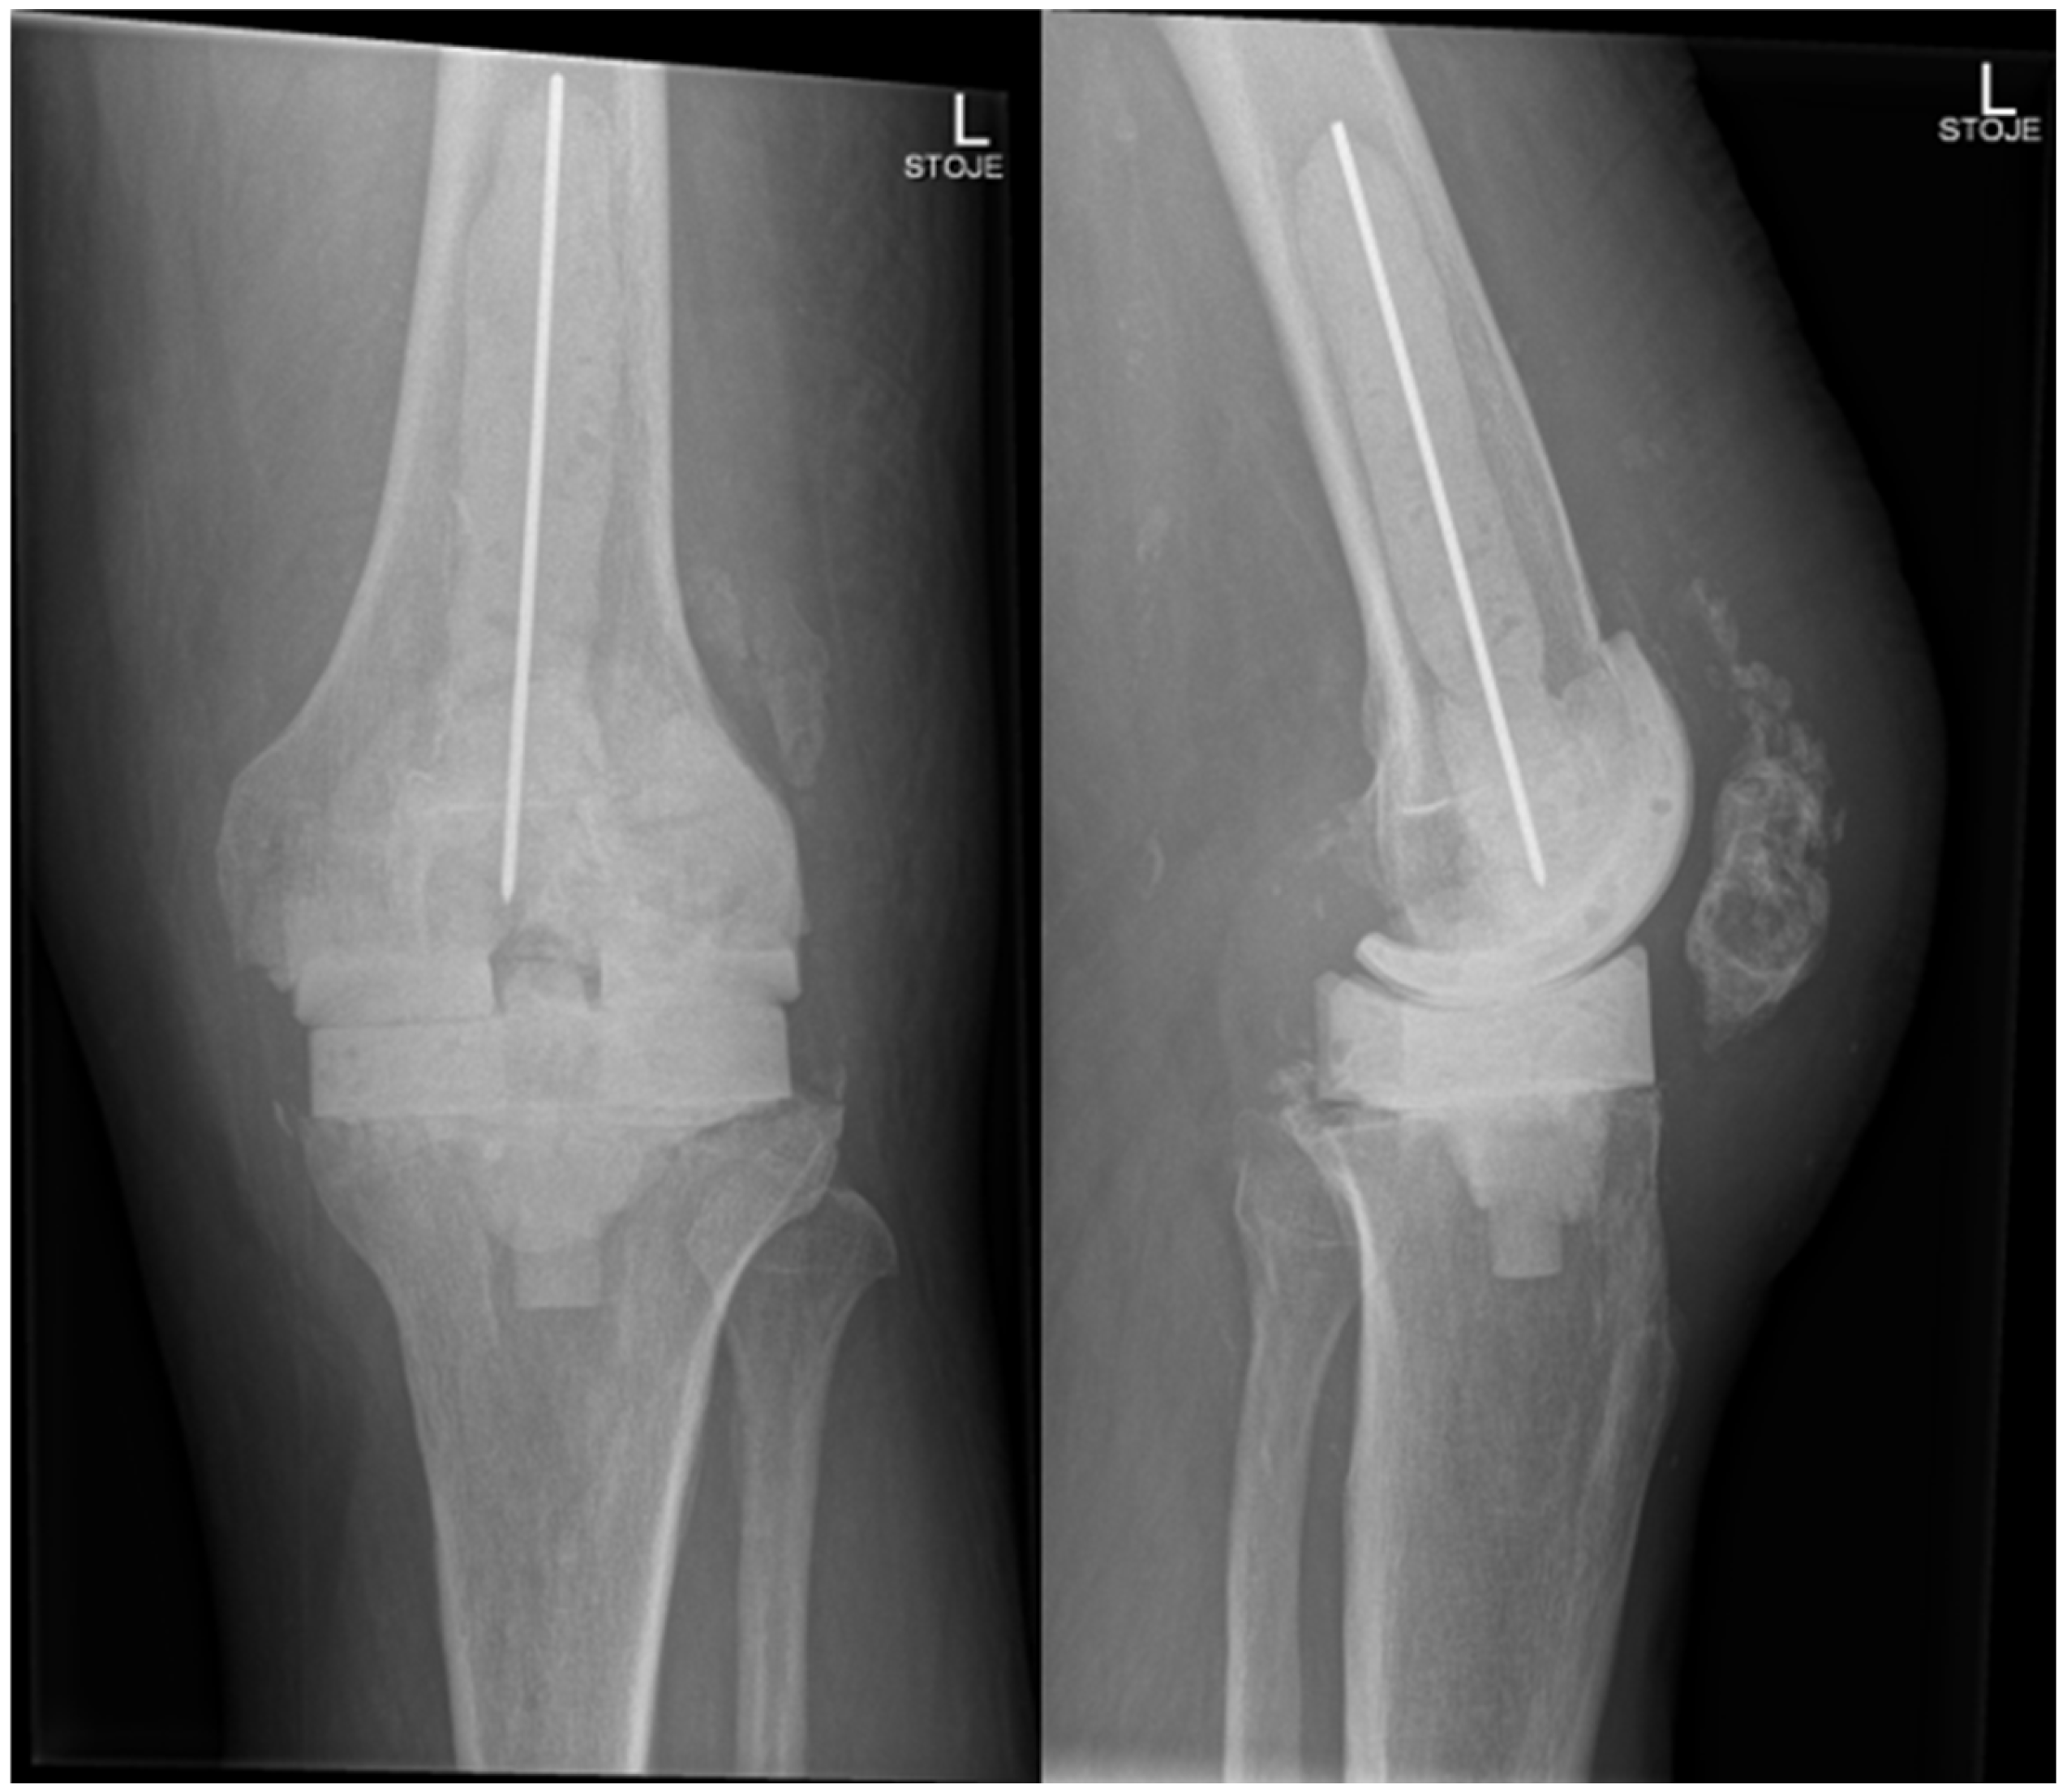

Candida parapsilosis grew in both synovial fluid samples from separate aspirations and was identified by standard microbiology methods at the microbiology laboratory at the National laboratory of health, environment and food, Maribor. Unfortunately, a mycogram was not obtained, as it is not performed in all samples routinely at the laboratory. According to the retrospective analysis of bloodstream fungal infection from central Slovenia, the Candida parapsilosis resistance rate to fluconazole was very low, and we decided to start the treatment preoperatively with oral fluconazole 400 mg/day [11]. A decision to perform a two-stage revision surgery with a 4-week interval was taken. The first stage was performed in October 2024, involving the complete removal of the implant, debridement, and insertion of an antibiotic- and antifungal-impregnated cemented spacer. For the spacer, we used Palacos R+G® cement (Heraeus Medical GmbH, Wehrheim, Germany), with each package containing 40.8 g of cement powder, 20 mL of monomer liquid, and 0.5 g of industrially premixed gentamicin. Additionally, we supplemented it with 0.25 g of non-liposomal amphotericin B deoxycholate powder (Fungizone®, Delpharm, Boulogne-Billancourt, France) per package. A total of three packages were used, resulting in a cumulative amphotericin B dose of 0.75 g. The cement powder, antifungal powder, and monomer liquid were thoroughly blended by hand, resulting in a yellowish-colored bone cement of proper hardness. In Figure 3, the preparation of an antifungal-impregnated cemented spacer is shown. During the operation procedure, 5 intraoperative tissue samples, synovial tissue samples, 2 bone tissue samples with residual non-resorbable suture material, and the explanted prosthesis were collected for further microbiological analysis; sonication of the explanted material was performed and sonication fluid cultured according to a standardized protocol. Candida parapsilosis grew from all tissue samples, bone samples, and from the sonication fluid of the removed implant in low concentration, 3 CFU/mL. Tissue samples were also sent for histopathology exam, and acute inflammation was confirmed. Antifungal therapy with intravenous caspofungin (70 mg) was started preoperatively, then 50 mg/day for two weeks, followed by an oral switch to fluconazole at 400 mg/day. The patient continued fluconazole therapy until the second stage of surgery, with no drug holiday before reimplantation was planned. In Figure 4, the left knee is presented in radiography after the first-stage surgery with insertion of an antibiotic- and antifungal-impregnated cemented spacer.

Figure 4. Radiography of the left knee—anteroposterior and lateral views of the knee after removal of knee endoprosthesis and insertion of an antibiotic- and antifungal-impregnated cemented spacer.